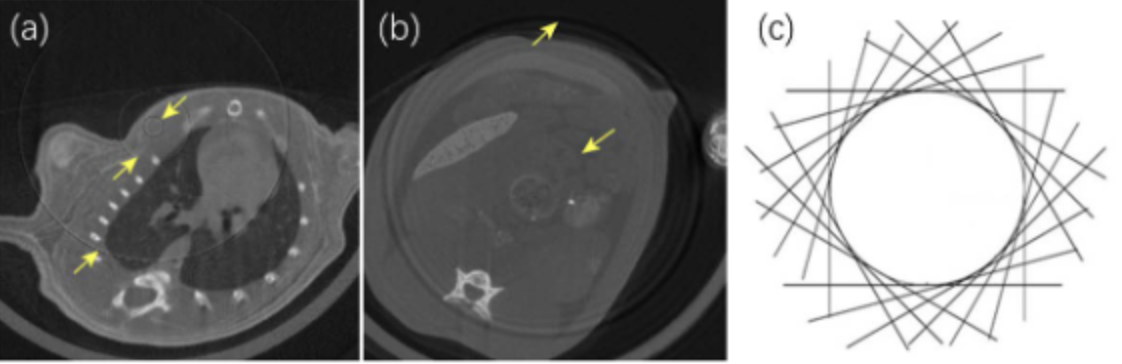

环状伪影示意图

(a)(b)环状伪影示意图;(c)环状伪影的成因。图片来源于文献【1】